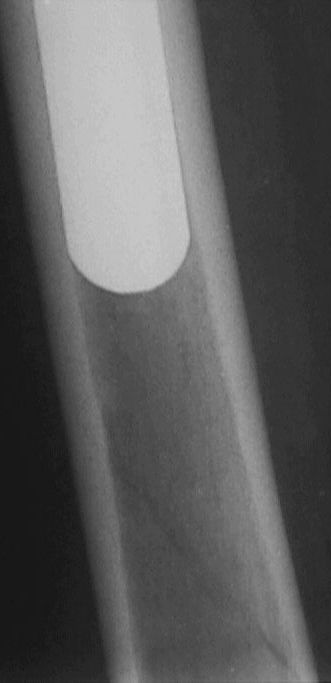

Больной оперирован в конце марта 2003 НИИТО г. Новосибирск. Не замечен перелом бедра р-ма 1.- 2 . (сделанных в НИИТО). Больному рекомендовали ходить приступая на конечность, отмечает усиление болей, появление укорочения.На контрольных рентгенограммах 19.05.03 рис 3 имеется перелом бедра со смещением, появлением периостальной мозоли. Больной ходит на костылях, приступая на конечность. Сгибание в т\б суставе 90 гр , сгибание в коленном суставе до 90 гр в положении стоя на костылях.Есть несколько вариантов.1. Провести открытую репозицию фиксацию пластиной с проведением винтов на уровне ножки протеза через кортикальный слой.2.Провести открытую репозицию фиксацию винтами с межфрагментарной компрессией. Думаем, как выполнить репозицию перелома по длине.3. Наложить кокситную повязку до окончательного сращения перелома4. Провести скелетное вытяжение репозицию.Сергей ЗыряновНовосибирская область г. Куйбышев ЦРБ

Рис-2 сделаны в НИИто через неделю после операции